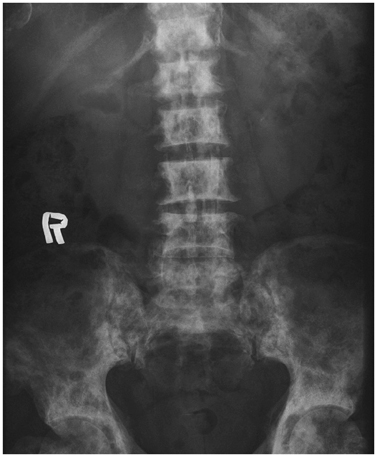

Systematic Approach of Sclerotic Bone Lesions Basis on Imaging Findings

- Sclerotic bone lesions are common, but there are diverse groups of tumors and non-tumorous lesions. Although plain radiograph and computed tomography can reveal important characteristics of these lesions, diagnosis is often challenging for radiologists. A systematic approach and familiarity with the imaging features of various sclerotic bone lesions may be greatly helpful for eliminating in the differential diagnosis. This review describes the systematic approach to diagnosing sclerotic bone lesions based on imaging findings.